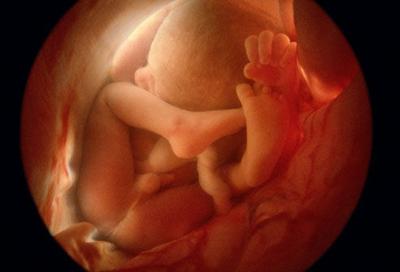

六、受精后6星期,人形已隐约可见。这时,胚胎的心跳每分钟140—150下.是母亲心跳的两倍。